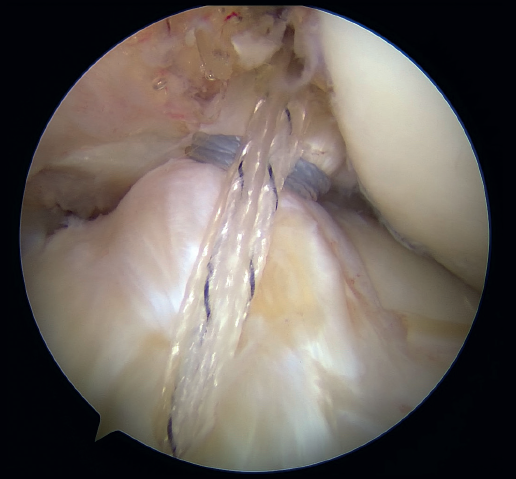

The anteromedial and posterolateral fascicles of the ACL are then identified for suturing separately. Using a suture passer, a closed loop suture is passed through the anteromedial fascicle at its most distal zone, and the loopless extremity is carried alternately (medial to lateral, lateral to medial and so on) to the most proximal zone, usually involving 3 or 4 passes of the suture. The thread may knot on itself during suturing if we are not attentive to it on entry and exit. To solve this problem, we simply undo the knot with retrieval forceps and repeat the step if necessary.

On completion, the thread is retrieved through the accessory anteromedial portal. The process is then repeated, this time with the posterolateral fascicle. To prevent the first thread from breaking with passage of the second thread, it must be ensured that entry and exit in the ligament are very posterior and ideally somewhat proximal to those used for the anteromedial fascicle. Once having reached the most proximal zone after 3 or 4 passes, retrieval is carried out in the same way through the accessory anteromedial portal.